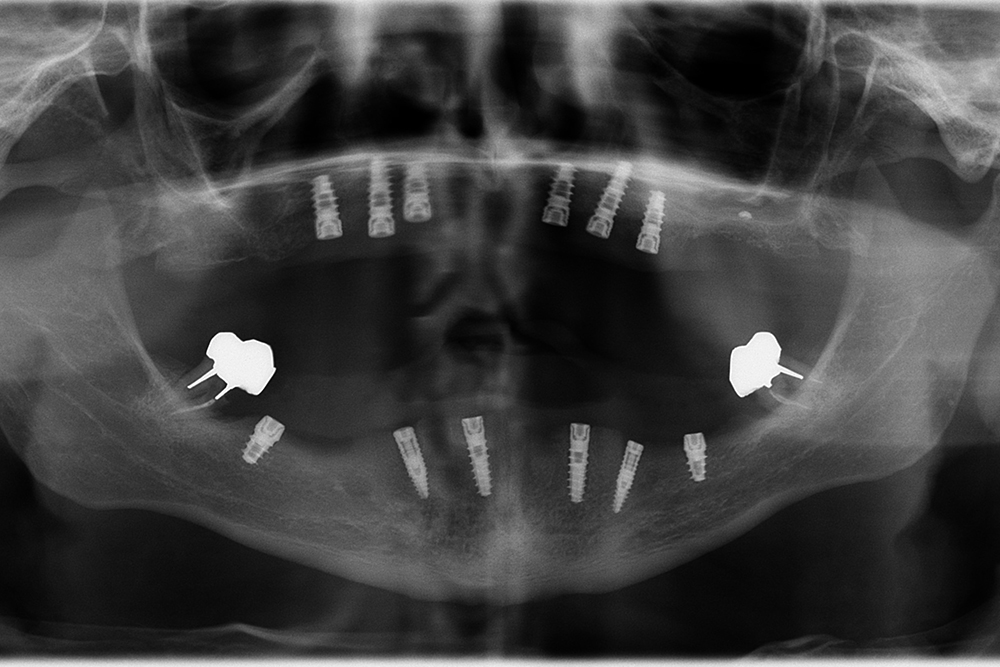

Ripristino dell'arcata superiore ed inferiore su impianti con ricostruzione estetica in zirconia e ceramica Category: Lavori ImpiantiMaggio 9, 2018Condividi questo ProgettoShare with FacebookShare with TwitterShare with Google+Share with PinterestShare with LinkedInProject navigationPreviousPrevious project:Ripristino dell’arcata superiore atroficaNextNext project:Protesi mobile superiore + Overdenture inferiore